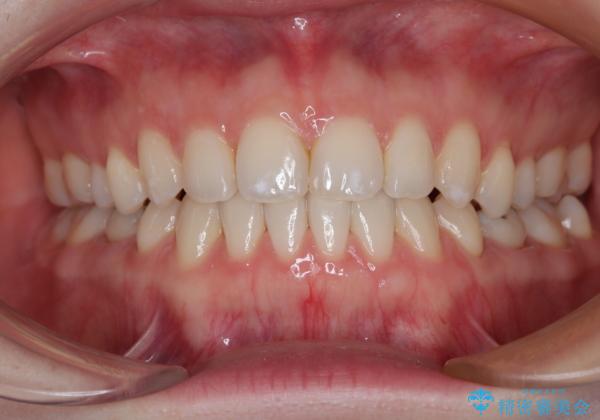

すきっ歯をインビザラインできれいな歯並びに改善

- 前歯の隙間を気にして来院された患者様です。

隙間や叢生の程度はそれほど著しいものではなかったので、インビザラインでもワイヤー矯正でも対応可能でしたが、極力目立たない装置を希望されたため、インビザラインにて矯正治療を行うこととしました。